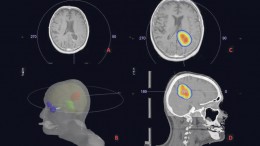

Richtige Ernährung unterstützt Krebstherapie

Ernährungsberatung in der Praxis für Strahlentherapie Harburg – Diplom-Ökotrophologin Magdalena Polkowski im Einsatz. Die Ernährung spielt eine wichtige Rolle bei der Behandlung…